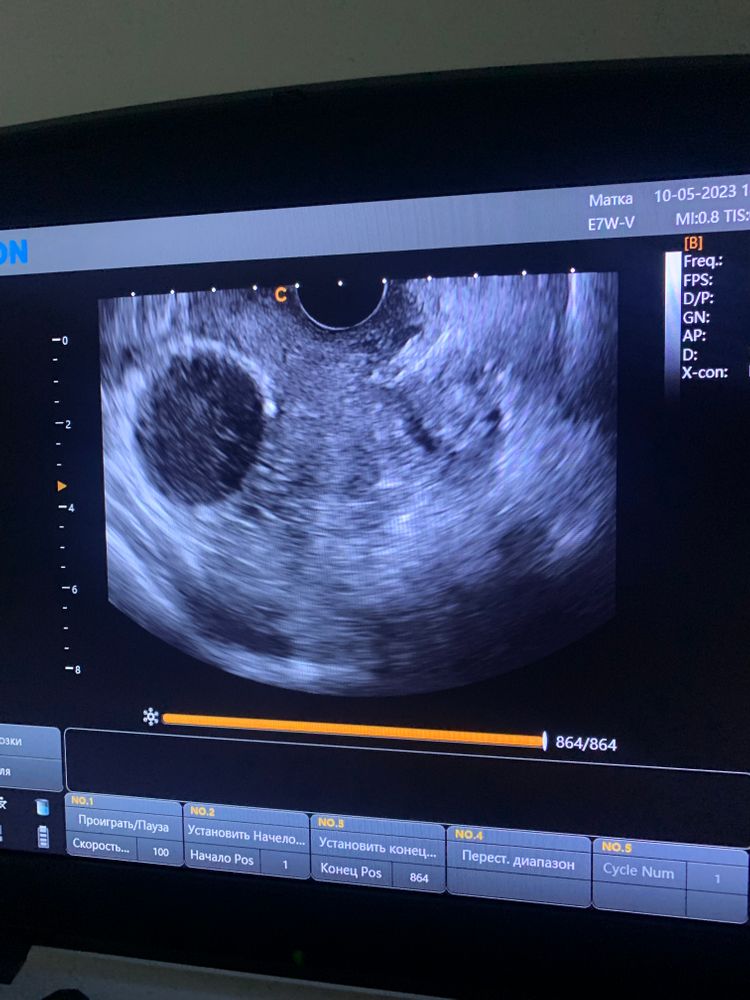

Киста желтого тела(эндометриодная?)

Здравствуйте . Кто сталкивался? Напугали кистой. До этого была киста ЖТ два цикла и исчезала после месячных. А теперь ставят другую под вопросом

Эндометриоидная за раз до таких размеров не вырастет. Они бывают похожи с кистой ЖТ, обычно еще кровоток смотрят. В любом случае узи в динамике, и будет понятно.